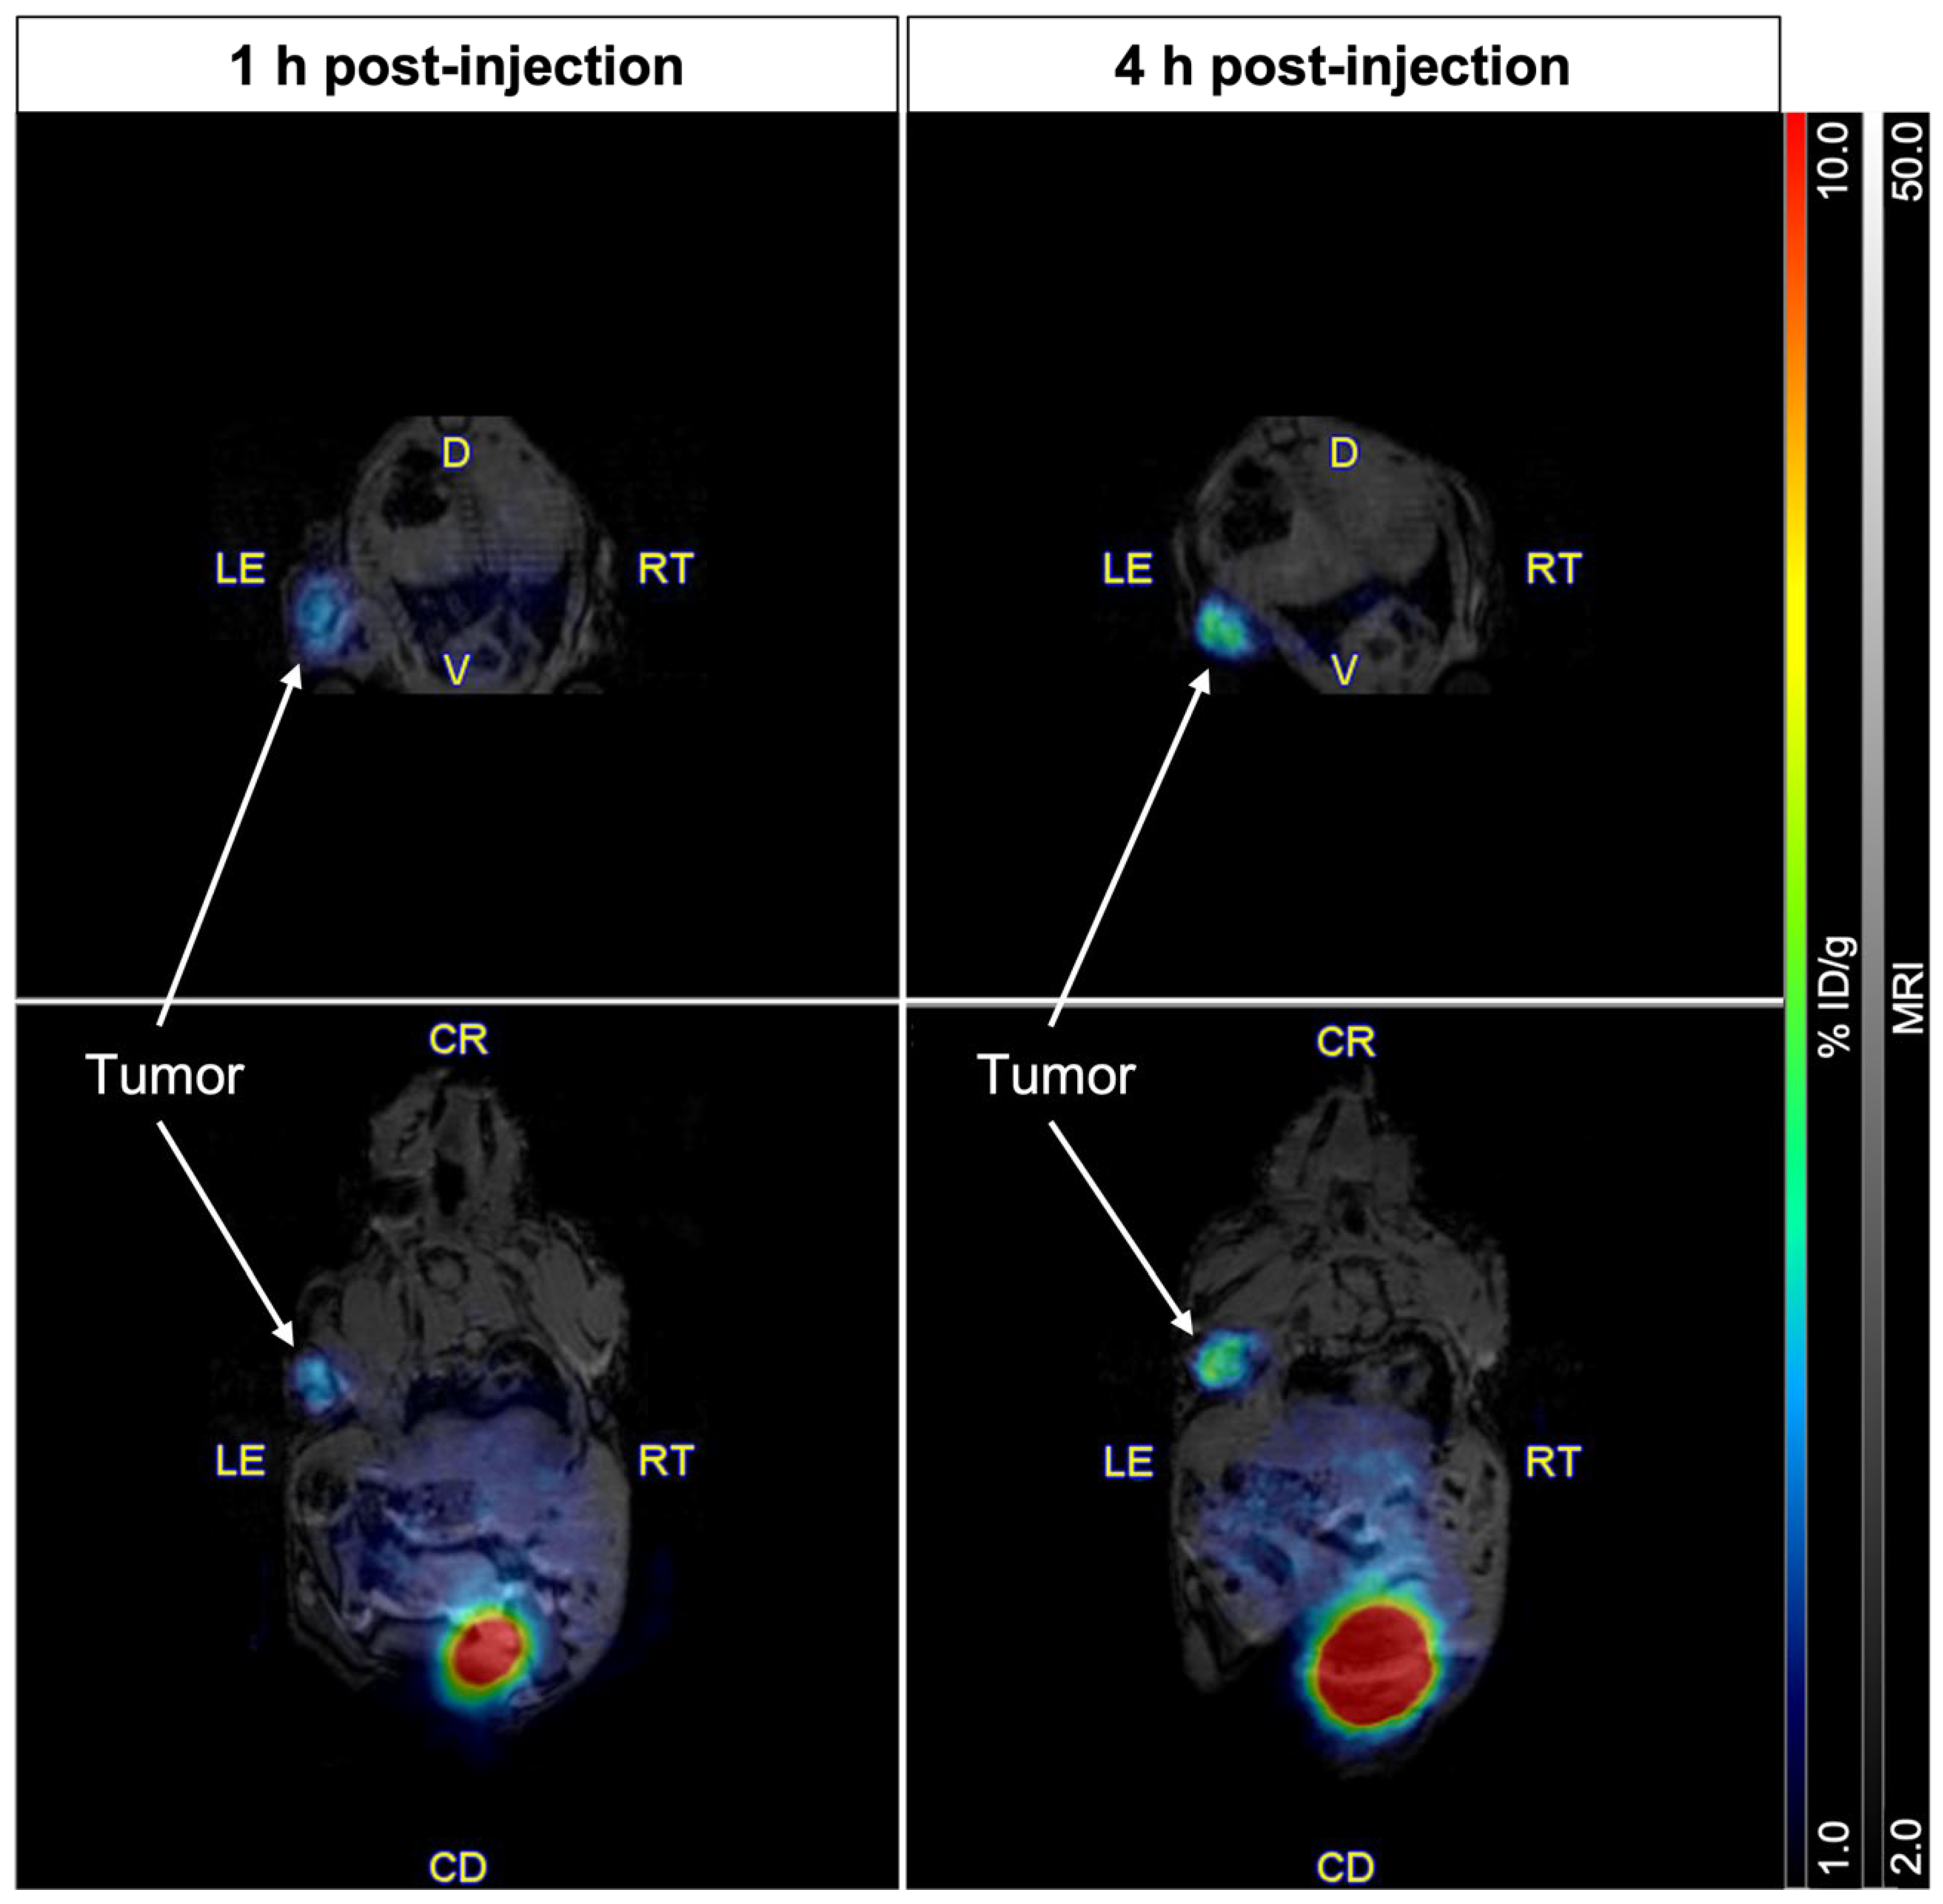

2.4. Imaging of PSMA Receptors with [61Cu]Cu-NODAGA-PSMA-I&T